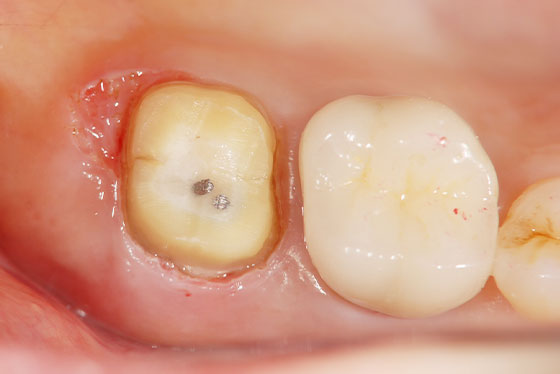

歯の上部が割れた場合と、歯の根が割れた場合とでは、治療法や治療の難易度が異なります。「歯の上部」が割れた場合は、基本的に抜歯せずに治療が可能です。しかし、「歯の根」が割れた場合、多くのケースは抜歯の選択となります。

しかし、「歯の根」が割れた場合でも、一度、その歯を意図的に抜歯し、割れた部分を処置して再度元に戻す「意図的再植術」を行うことで最終的には抜歯せずに治療ができることもあります。

以下、他院で「抜歯」と言われた歯を残したケースになります。

他院で「歯の根が割れてるので、抜歯になります」と言われた場合でも、実際は割れておらず、通常の根管治療で対応ができる場合があります。